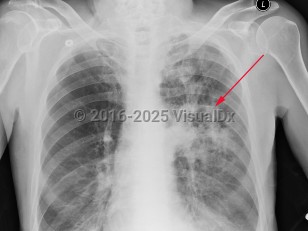

Chest pain, Pleural effusion, 50-59 year old Female

Pleural effusionPleural effusion

Congestive heart failureCongestive heart failure

Pulmonary edema

Pulmonary embolismPulmonary embolism